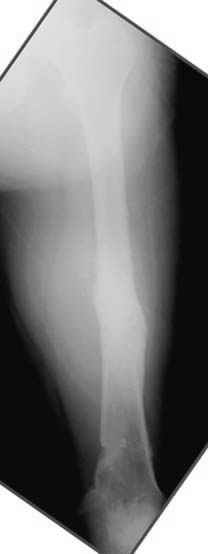

пластическая модель; и коррекция бедра аппаратом Илизарова.

хотя даже если бы и инфекция , то nail exchange с рассверливанием канала - вариант дебрайдмента) Я думаю, что последовательность развития событий:

Узкий к-м канал - тонкий гвоздь- усталостный перелом дистальных винтов - развитие нестабильности и как ее результат остеолиз вокруг гвоздя - деформация анатомической оси бедра. Похоже, что я понял почему аппарат, а не новый гвоздь:-)